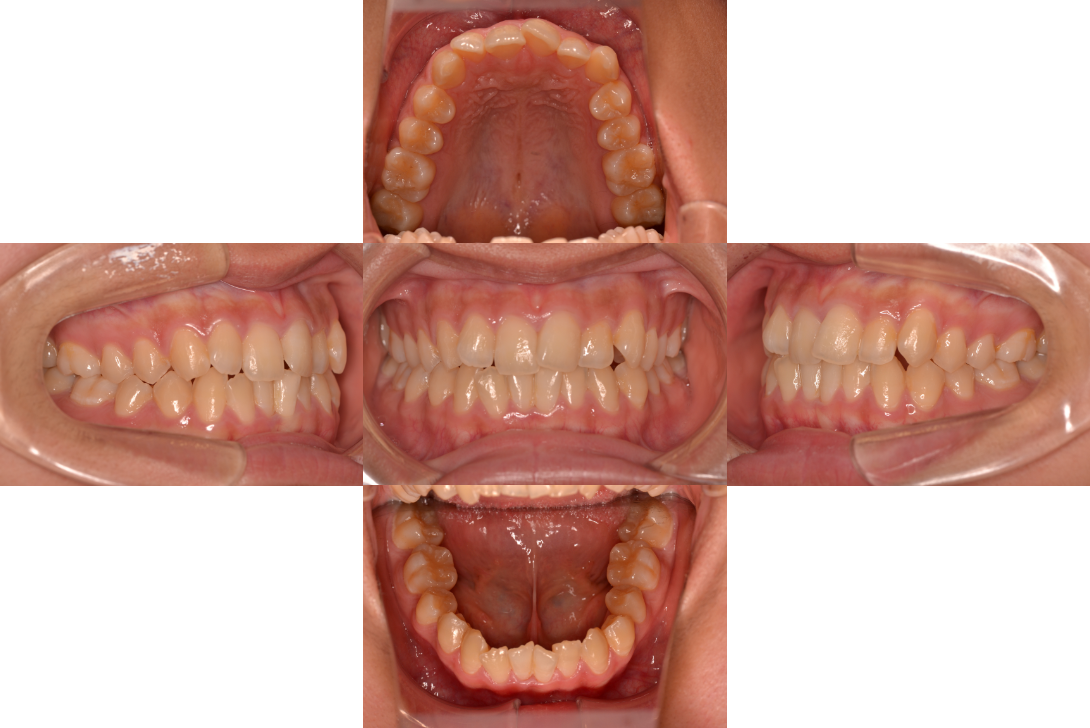

叢生をフルDBSで改善した症例

※DBSとはダイレクトボンディングシステムと呼ばれており、ブラケットにワイヤーを通して歯を動かしていく矯正治療です。

患者情報

21歳女性

主訴

ガタガタしている

行った治療内容

フルDBS

治療のリスク

歯肉退縮、歯根吸収

治療期間

動的治療期間2年4か月

※ クリックして拡大することができます。